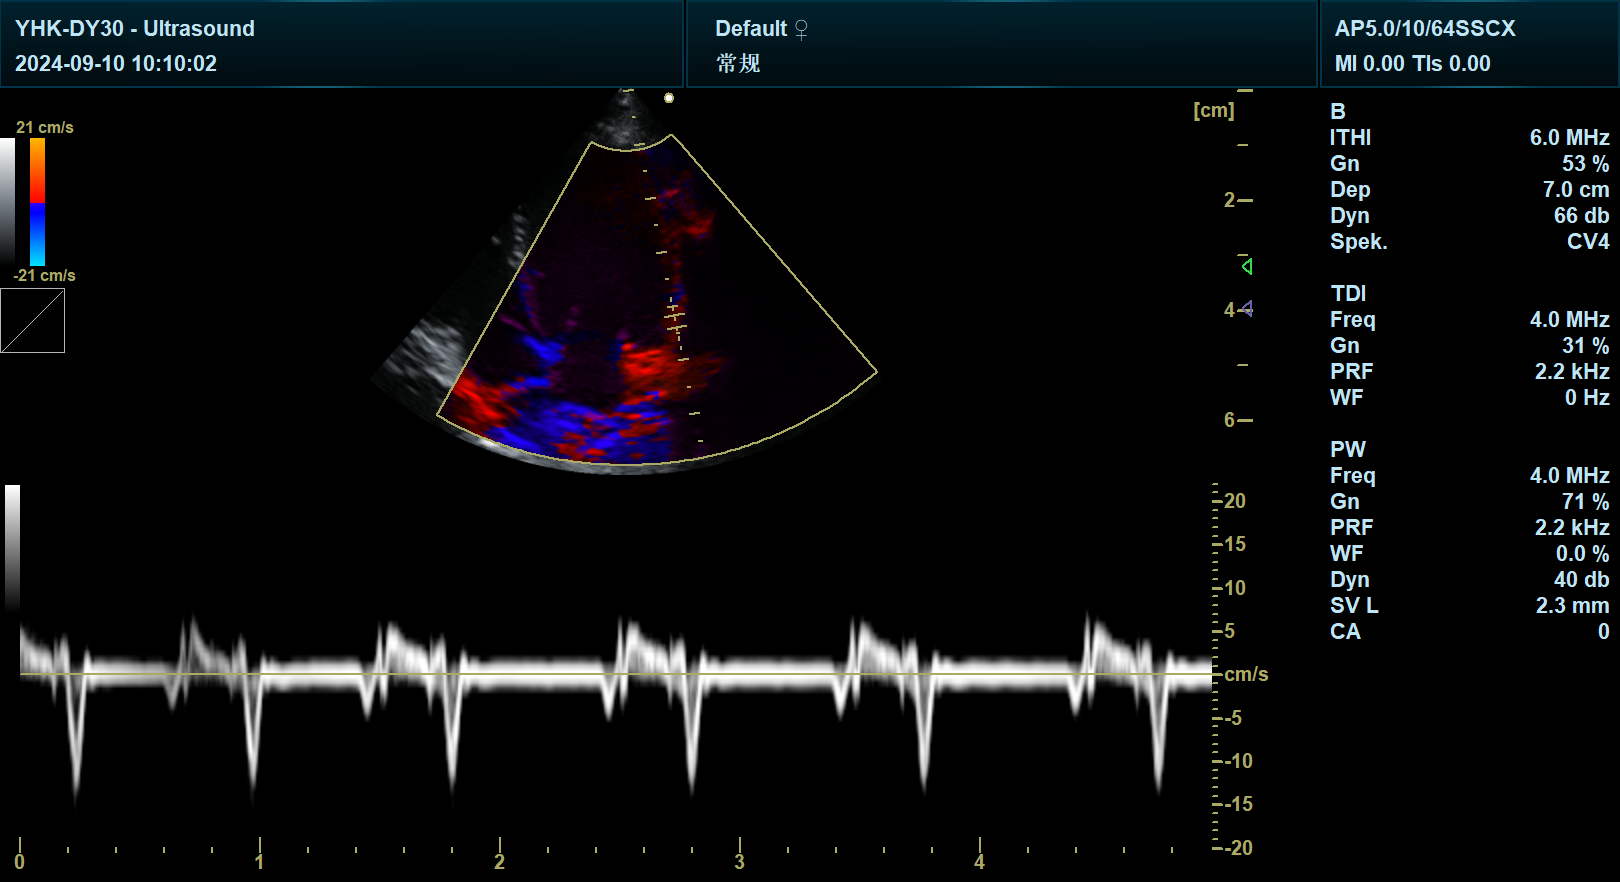

宠物彩超在心脏疾病的诊断中具有重要地位。心脏彩超不仅可以观察心脏的形态、大小和结构,还能检测心脏的血流速度和方向,为兽医提供心脏功能评估的重要依据。这对于及时发现并治疗宠物心脏疾病具有重要意义。